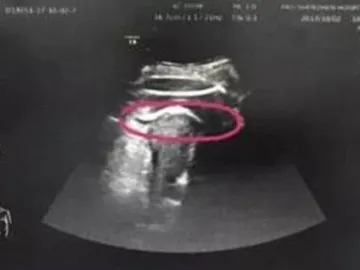

Una mujer embarazada, a punto de morir tras recibir una fortísima patada del feto en el útero